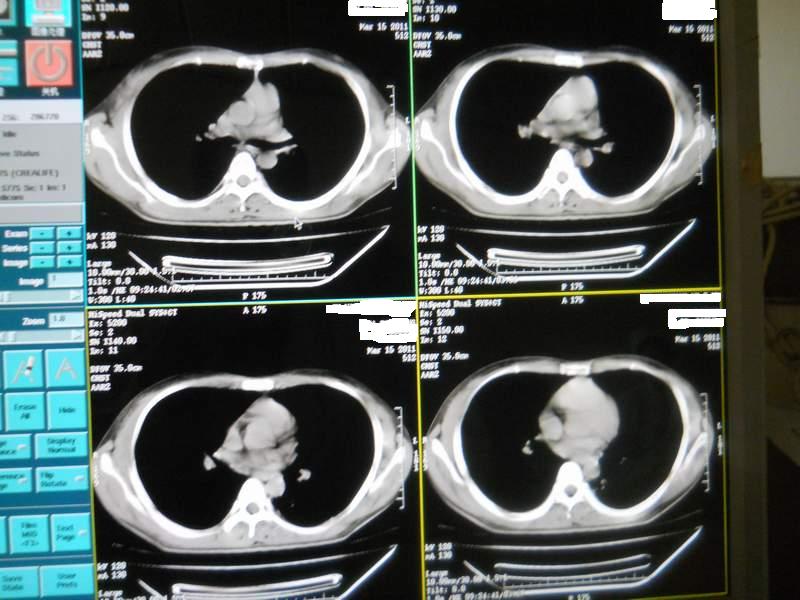

肺霉菌感染

男,22岁,一年前诊断马尔菲尼青霉菌感染,多次复查CT。多次HIV阴性。最近两次CT图片。有实验室结果。

最近实验室检查结果:霉菌感染。